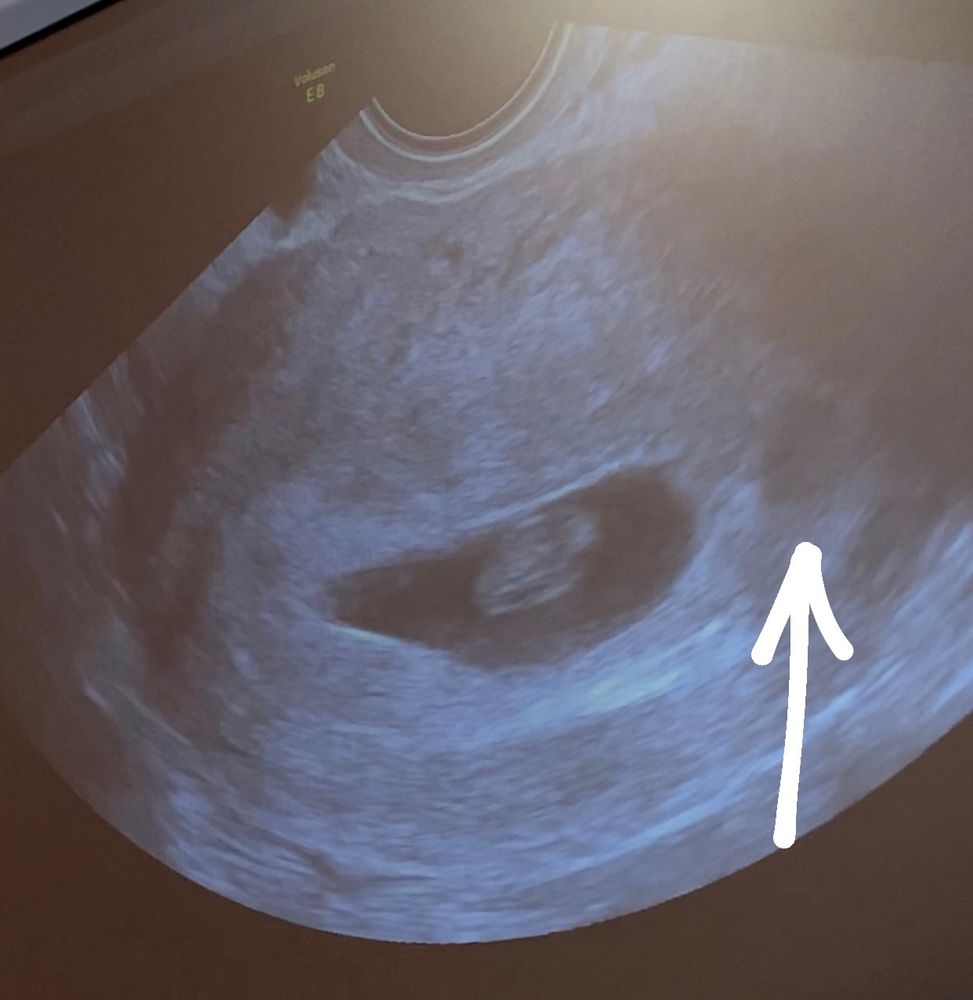

Отслойка, 7я неделя

Была сегодня на узи. Все хорошо с моим малышом, ктр 10 мм, сердцебиение 142 уд. Однако, около породного яйца есть отслойка…Доктор сказала , что она не большая, не паниковать и начать пить дюфастон и ректально свечи папаверин. *скрин из моего видео узи*

девочки, у кого на раннем сроке была отслойка? Все ли хорошо было потом? Как лечились? И не странная ли форма плодного яйца…какая-то продолговатая…